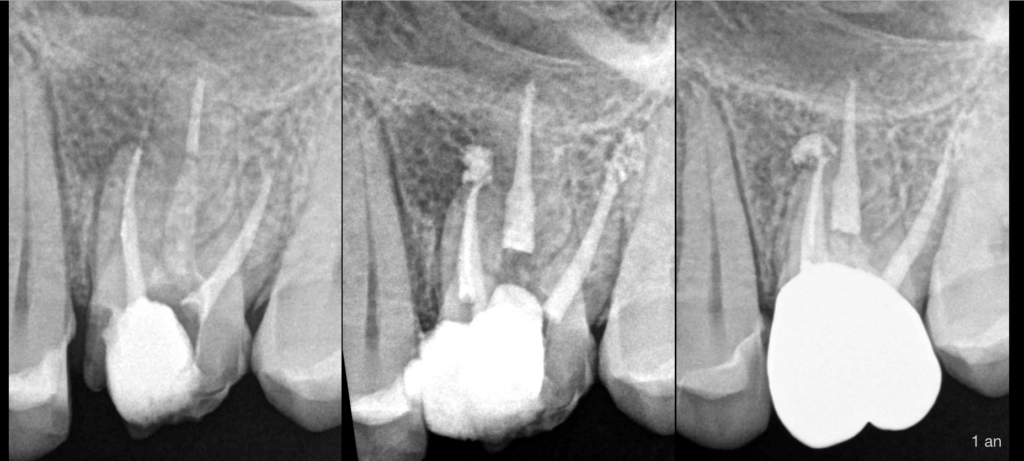

🔍 Pulpe précédemment traitée, parodontite apicale symptomatique (racine MV).

MV2 non traité.

➡️ Retraitement canalaire.